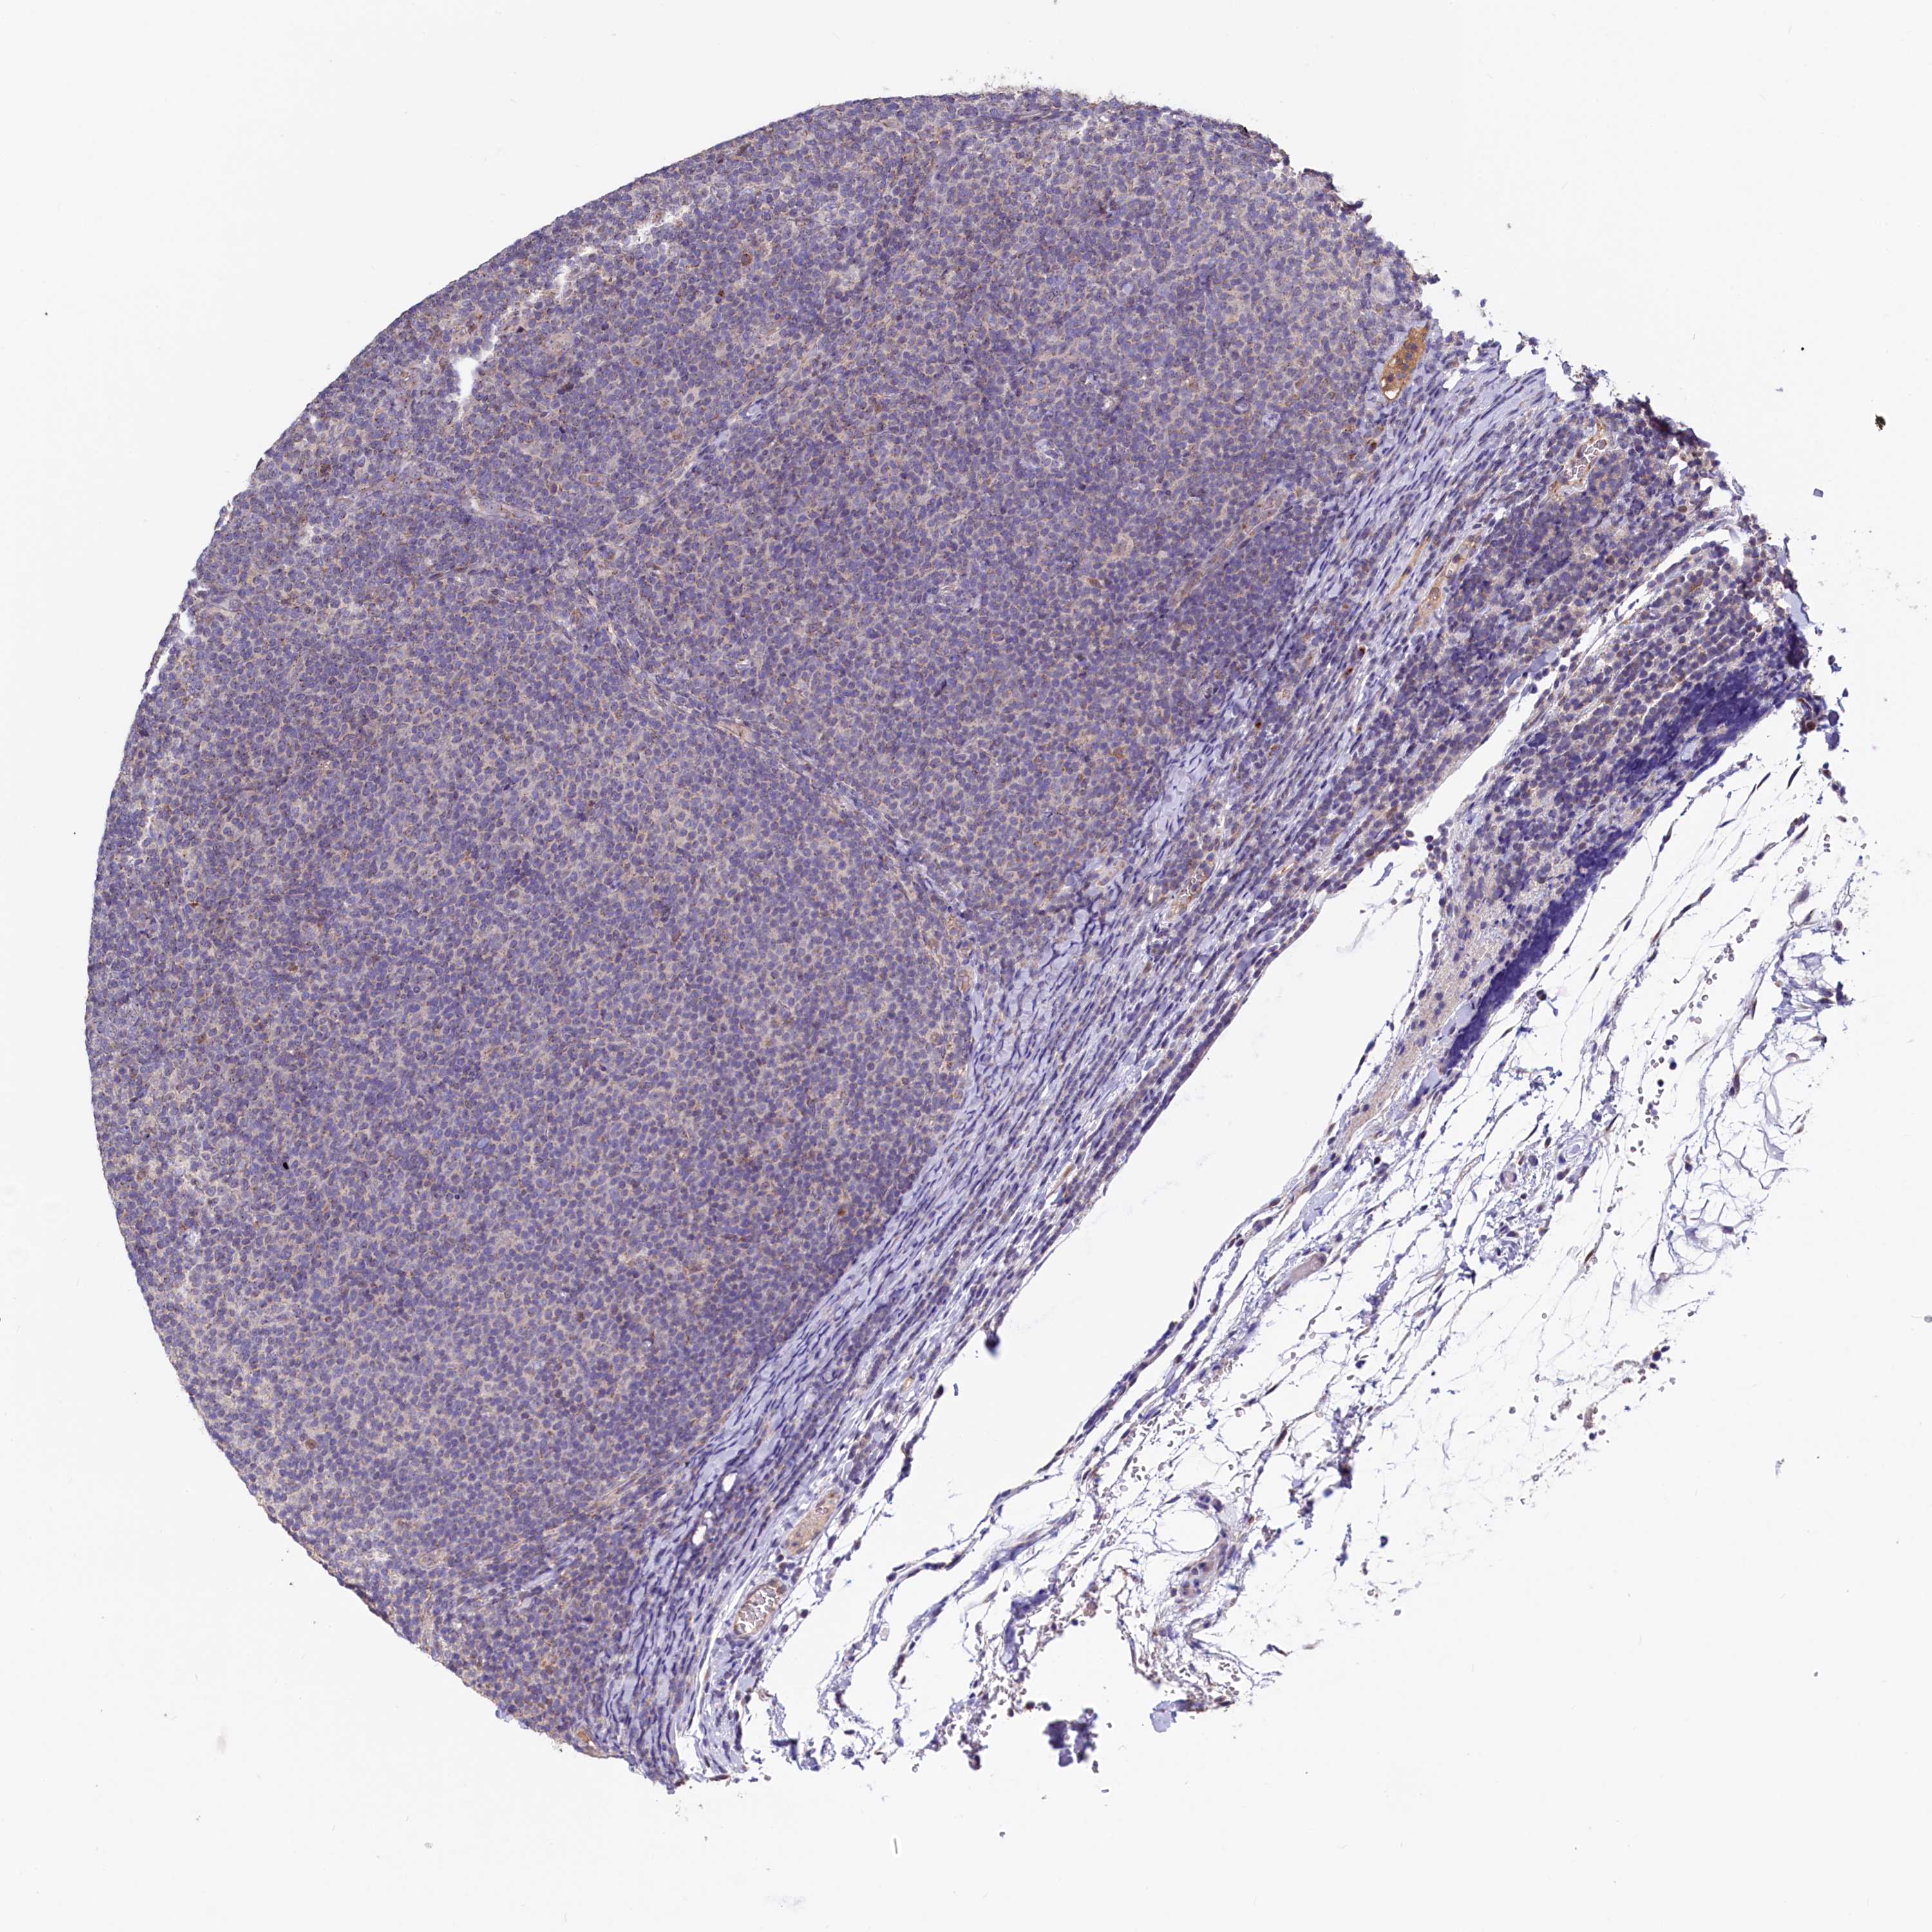

CANCER LYMPHOMA Show tissue menu

LYMPHOMA - Protein expressioni

A mouse-over function shows sample information and annotation data. Click on an image to view it in a full screen mode. Samples can be filtered based on level of antibody staining by selecting one or several of the following categories: high, medium, low and not detected. The assay and annotation is described here.

Each image is clickable and will lead to virtual microscopy that enables deeper exploration of all samples and also displays staining intensity scores, fraction scores and subcellular localization as well as patient and tissue information for each sample.

Antibody HPA040213

Hodgkin's disease, NOS

Malignant lymphoma, non-Hodgkin's type, High grade

Malignant lymphoma, non-Hodgkin's type, Low grade